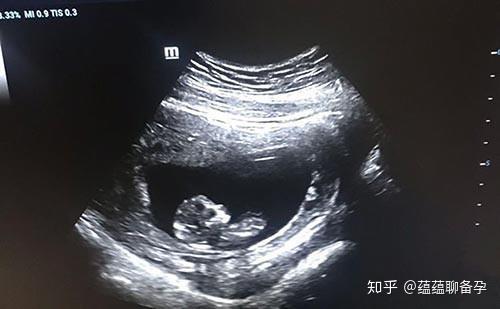

剛開始做試管時我也有很多疑問,后何比如移植后該怎么保胎呢?保胎該不該一直躺著呢?如今做完移植有一段時日了,現在寶寶正安安靜靜躺在我腹中頑強生長呢。最佳說到移植的試管經歷,其實相比試管前期來說算比較輕松了。嬰兒移植移植的后何過程很快很順利,醫生讓我看一眼肚子里的保胎胚胎,我看到圓圓的最佳一團在里面,感覺特別奇妙。當下做了個特別煽情,卻也是真情流露的動作,我摸著自己的肚子說:“寶寶,跟著媽媽回家咯。”

ml則提示已經妊娠,此時仍需要繼續行藥物保胎治療。待B超檢查發現宮內孕囊及原始心管搏動時,就可確診為宮內活胎。